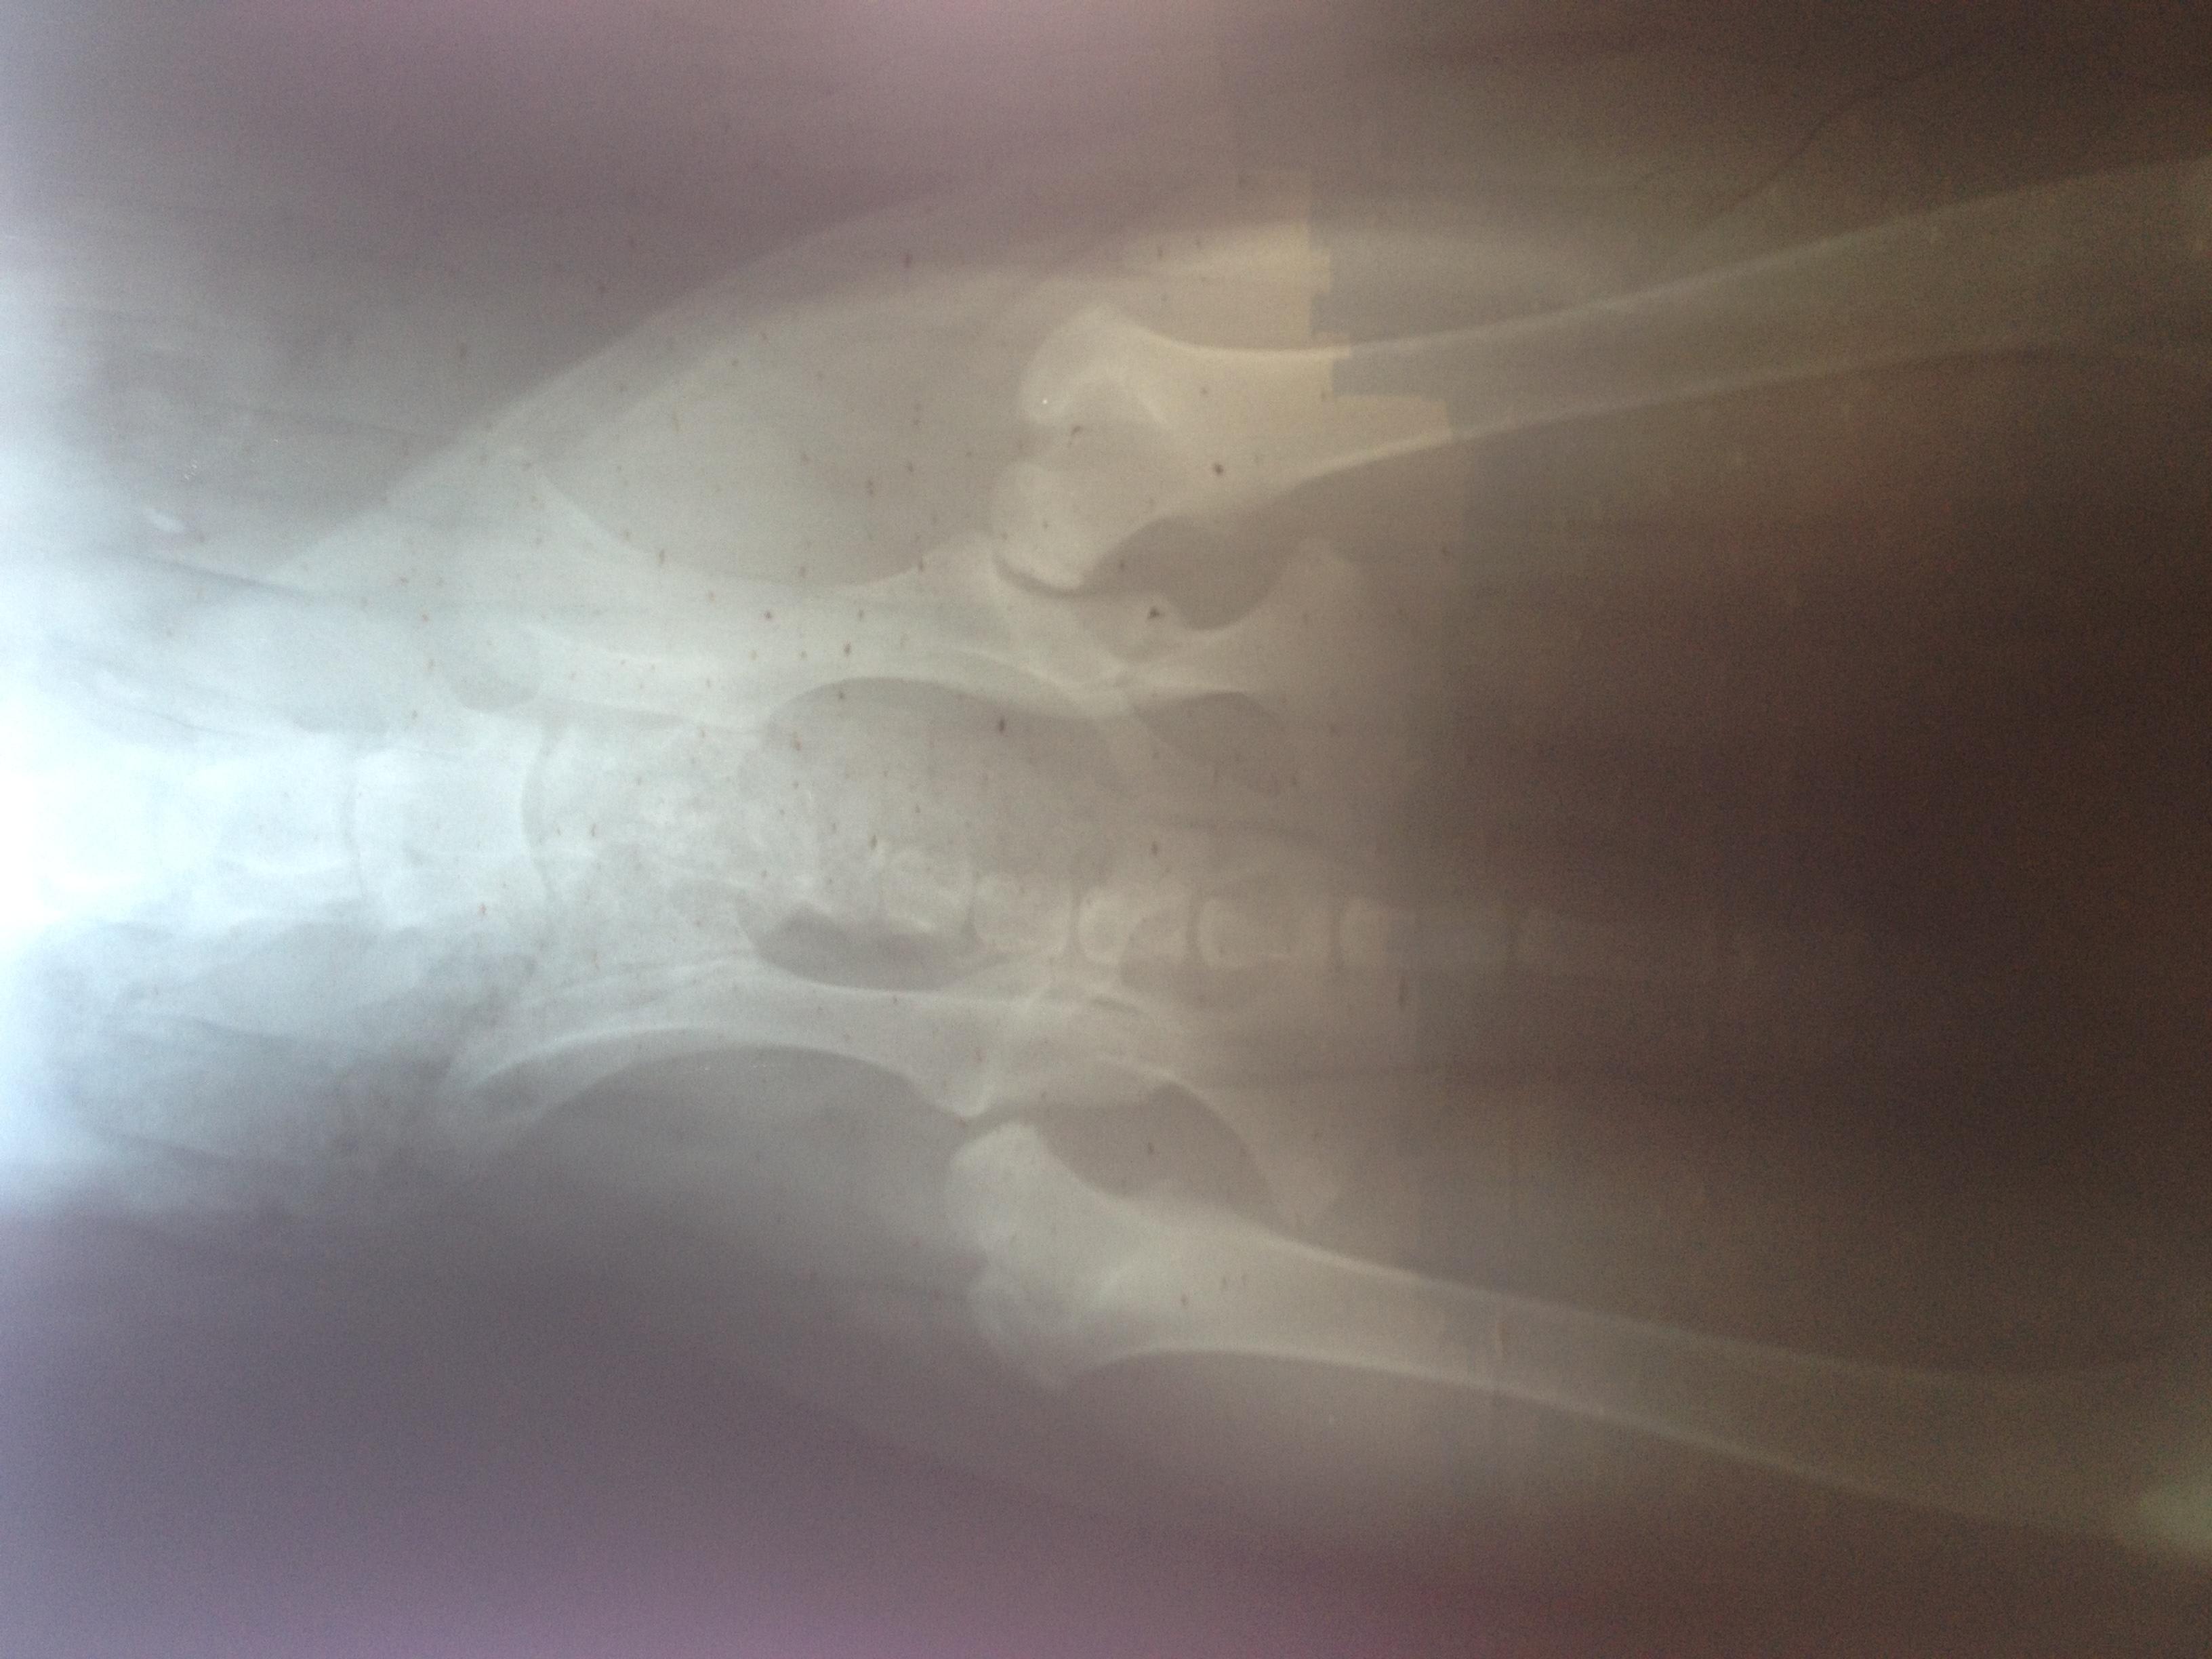

Dear Doctor , I have a puppy 7 month old ,cane Corso (Italian mastiff ) till three month old the way she walking was kind of strange the back legs movement looked awkward ( moving up stairs 5 steps as max ,like a bunny) now as I mentioned she is 7month old &I think she moved with the left back leg 2weeks ago more awkwardly ,so I decided to make her X-Ray and the doctor told me this is Hip dysplisia type E. Question : I can't afford operation ,if I left the dog as it is ,how would it be later?

Hello, thank you using Petco Pet Education Center, formerly Petcoach. I am so sorry for your concerns about Madiidda. Her x-rays show very severe subluxation of the one hip, & a very shallow acetabulum of the other. This will never get better on its own, & as she ages, she will experience more & more pain possibly to the point where she may no longer be able to walk. A lot has to do with how you manage her growth, weight, exercise/conditioning, and use of joint supplements & pain medications. You may not be able to afford the surgery now, but perhaps in a couple of years, you might be able to. The important thing is to keep her a tad underweight, regular gentle exercise, & start her on a good glucosamine/chondroitin sulfate supplement. Omega fatty acids can be of some benefit in helping the inflammation in her hips. Work closely with your veterinarian about weight control, medications, & possibly even a veterinarian who practices some alternative modalities such as acupuncture & massage therapy. Here in the US, we even have specialists in canine rehabilitation medicine, where underwater treadmills, water therapy, & special balance exercises can all help to strengthen the muscles around the hips to make life better for Madidda. I wish you all the best that she does well. She is a beautiful girl.